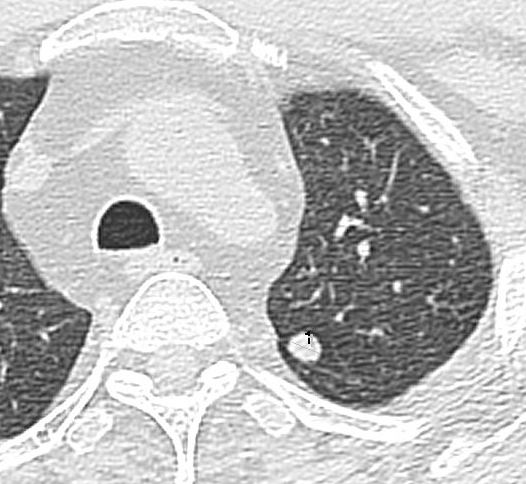

d. Finally, use words like ‘indeterminate’ if you cannot be sure of the diagnosis. So a single 4 mm pulmonary nodule in a patient with rectal cancer (note that this is statistically more likely to be benign) should be stated as ‘Indeterminate 4 mm pulmonary nodule, too small to characterize and needs to be followed-up after 3 months to rule out metastasis’ rather than directly calling it metastasis and confusing everyone. A larger 7-8 mm nodule can also be called indeterminate, with a recommendation for biopsy rather than short-interval follow-up given the higher likelihood of it being metastasis.

Here is an example of a right upper lobe 8 mm nodule (left image) in a patient with pancreatic cancer. Deemed metastatic on the outside report, we called it indeterminate and recommended biopsy (this was the only site of potential metastasis). The nodule had shrunk to 4 mm at the time of the biopsy (right image); we called off the biopsy and called it benign!